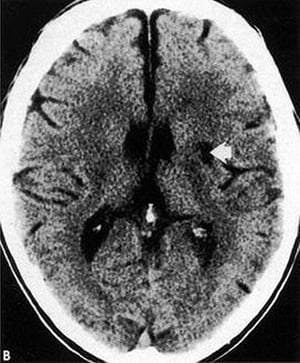

Verlust des Inselbandes

Diese CT-Aufnahme zeigt eine Auslöschung der Sylviasfissur und des Inselbandes (gerade Pfeile) auf der infarzierten Seite des Gehirns im Vergleich zum normalen Inselband (gebogene Pfeile).

By permission of the publisher. From Geremia G, Greenlee W. In Atlas of Cerebrovascular Disease. Edited by PB Gorelick and MA Sloan. Philadelphia, Current Medicine, 1996.